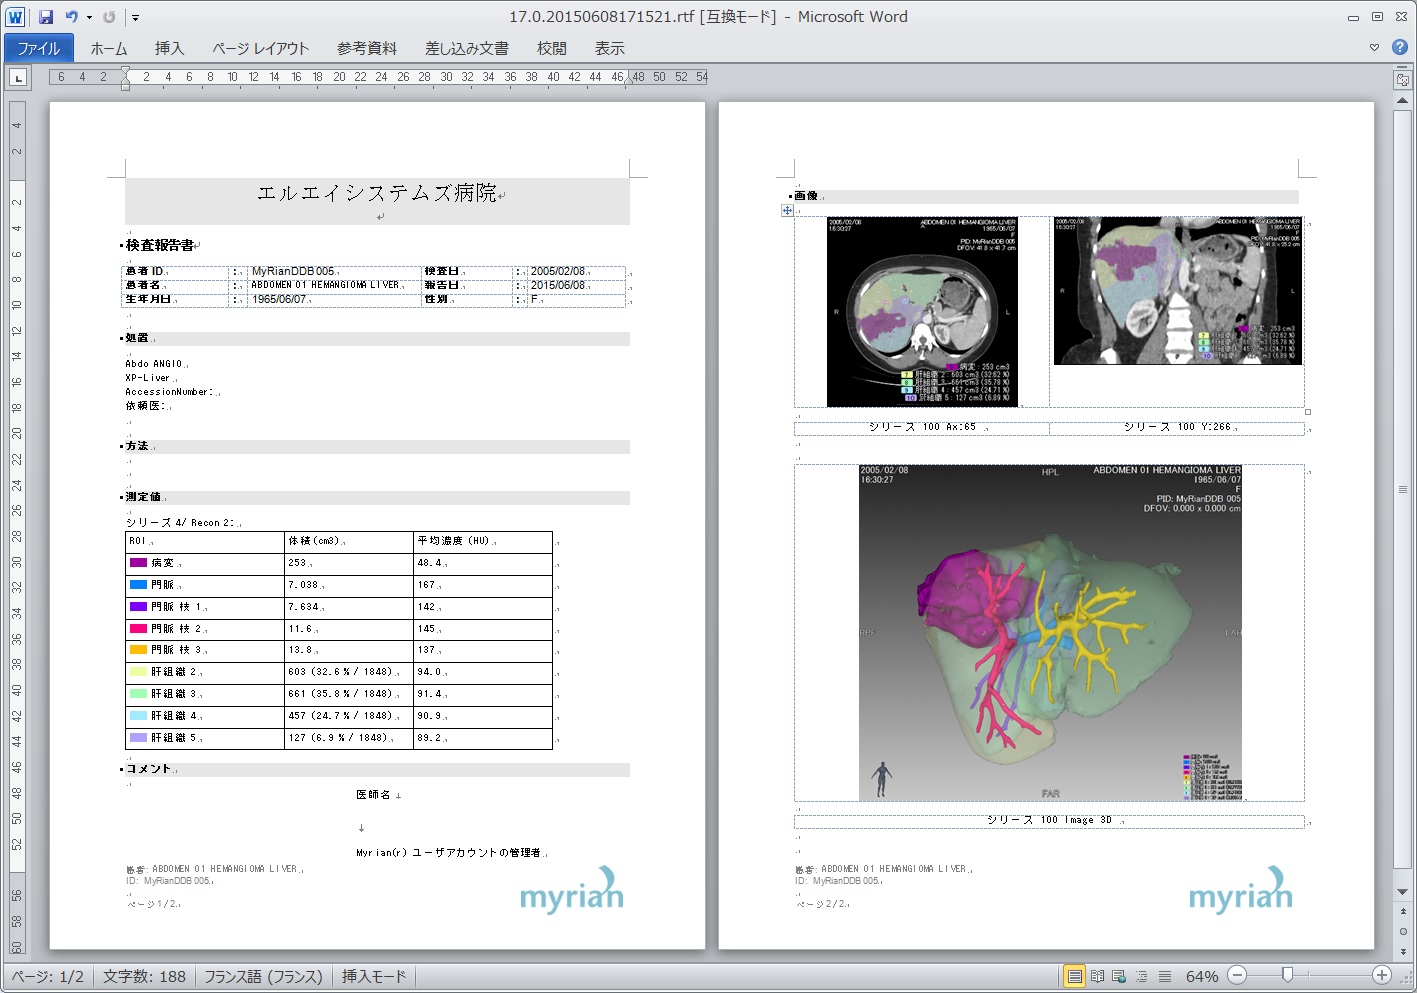

Myrian®XP-Liver 肝臓アプリケーション

世界的な実績と評価を得ている、肝臓解析と手術計画用ソフトウェア

独自に開発された、正確な非剛体レジストレーションと優れたセグメンテーション・アルゴリズムにより肝血管系、肝実質、腫瘍などを数秒で抽出します。

| 5.術前手術 シュミレーション |

|

|

|

| 6.3D PDF,ワードなど柔軟な レポート |

|

|